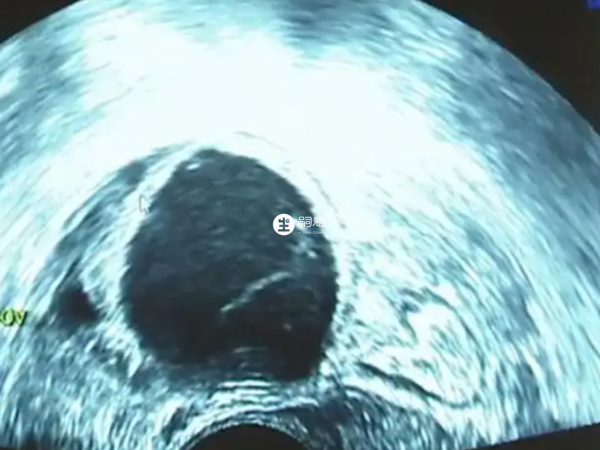

卵泡黃素化就是是指卵泡成熟直徑達到25mm以上還沒有破裂排卵而原位黃素化,而臨床上也可能對於卵泡黃素化沒有很好的給予診斷,所以造成誤診的情況,最終居然是懷孕的結果。b超卵泡黃素化卻懷孕了,可考慮為以下三種情況: